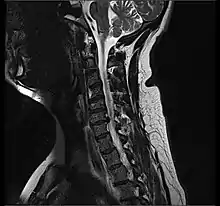

- Magnetic resonance imaging is the gold standard study for confirming a suspected LDH. With a diagnostic accuracy of 97%, it is the most sensitive study to visualize a herniated disc due to its significant ability in soft tissue visualization. MRI also has higher inter-observer reliability than other imaging modalities. It suggests disc herniation when it shows an increased T2-weighted signal at the posterior 10% of the disc. Degenerative disc diseases have shown a correlation with Modic type 1 changes. When evaluating for postoperative lumbar radiculopathies, the recommendation is that the MRI is performed with contrast unless otherwise contraindicated. MRI is more effective than CT in distinguishing inflammatory, malignant, or inflammatory etiologies of LDH. It is indicated relatively early in the course of evaluation (<8 weeks) when the patient presents with relative indications like significant pain, neurological motor deficits, and cauda equina syndrome. Diffusion tensor imaging is a type of MRI sequence used for detecting microstructural changes in the nerve root. It may be beneficial in understanding the changes that occur after herniated lumbar disc compresses a nerve root, and might help in differentiating the patients that need surgical intervention. In patients with a high suspicion of radiculopathy due to lumbar disc herniation, yet the MRI is equivocal or negative, nerve conduction studies are indicated.[43] T2-weighted images allow for clear visualization of protruded disc material in the spinal canal.

MRI scan of cervical disc herniation between C5 and C6 vertebrae.

MRI scan of cervical disc herniation between C6 and C7 vertebrae